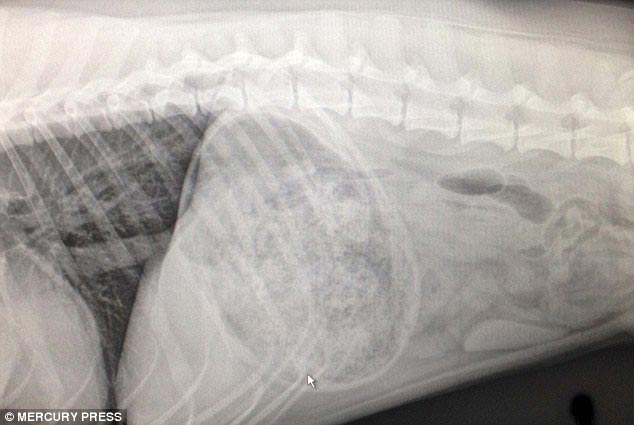

1 место - доберман Зевс, съевший 26 мячей для гольфа

Все 26 мячей извлеченные из его живота

![Что на ужин? Рентгеновские снимки животных, с шокирующими предметами извлеченными из их желудков предметы извлеченные из желудков животных, рентгеновские снимки животных съевших предметы, необычные предметы съели животные]()